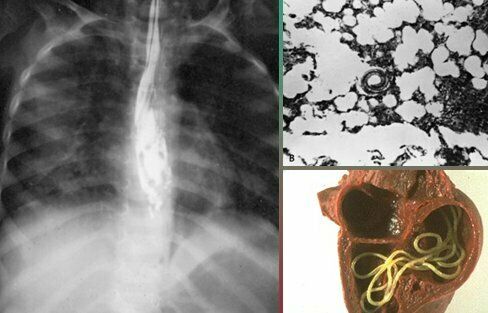

Menciona 3 parásitos que pueden causar cuadros de neumonía Ascaris lumbricoides Pneumocystis jirovecii Strongyloides stercoralis